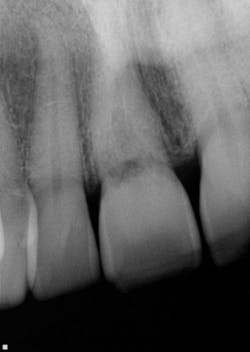

This actually has a huge bearing on dealing with resorption. External resorption versus internal resorption—when diagnosing, it makes all the difference. In my hands (and heart), I believe the only type that stands any chance whatsoever of treatment success is internal resorption. And even then, it depends on the extent of the damage.

When evaluating and discussing external resorption, I commonly tell my patients, “I cannot make your bones and gingiva stop eating the tooth. I do not have that power.” As we have all seen, external resorption can occur in various places and teeth. However, it almost always seems to be around the area of the alveolar crest, which, in my opinion, makes restoring it almost impossible. At least with internal resorption, one has a chance. You must be aggressive in cleaning the canal way beyond the typical endo and particularly in the areas of the defect. That, my friends, is where the microscope comes in very handy.

Unless it is caught on the early end, it does not matter. Once the resorptive damage has extended beyond a certain point, the prognosis drops precipitously, regardless of whether it started internally or externally. If communication of the defect occurs from internal to external or vice versa, I find that the prognosis goes from questionable to hopeless.